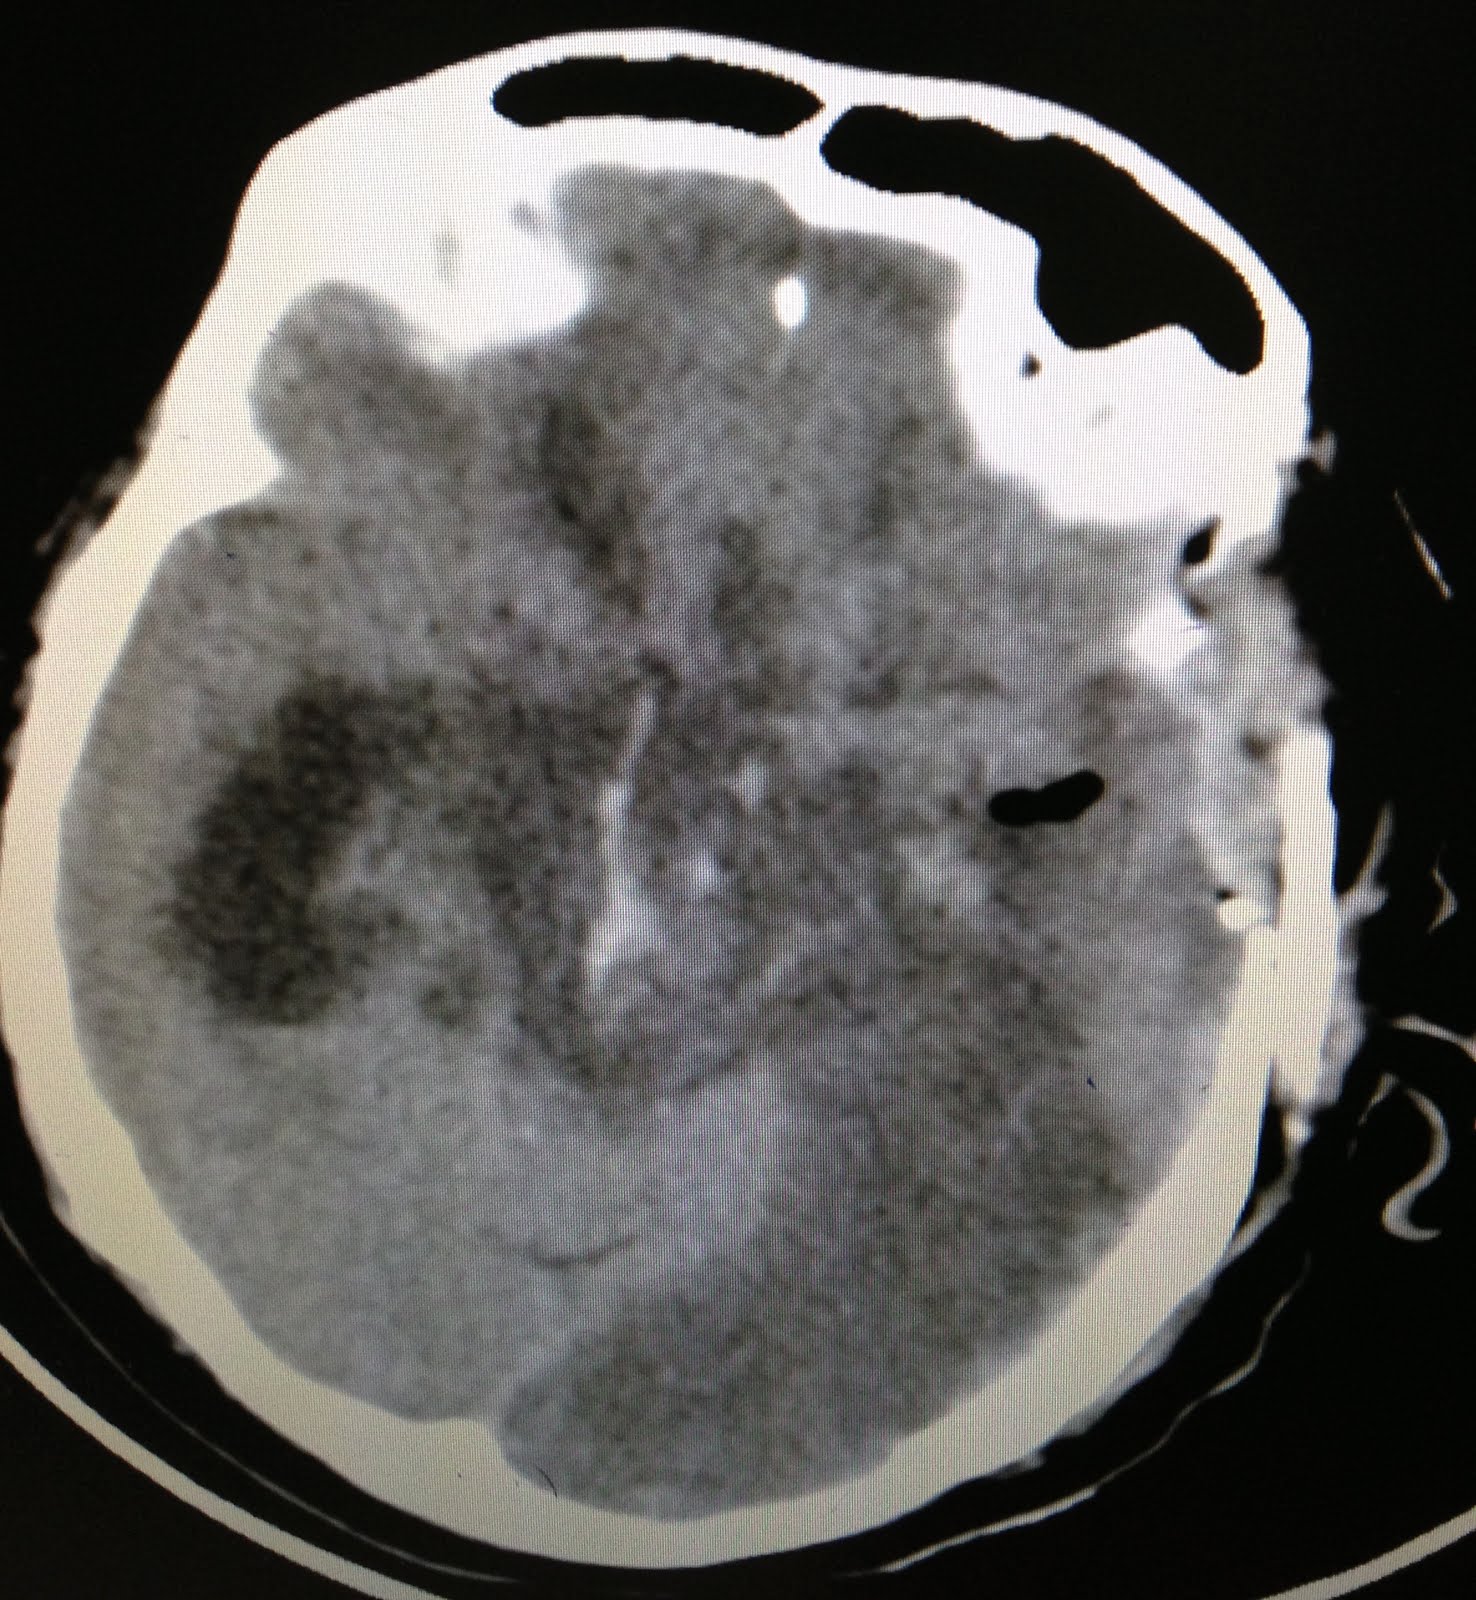

A 70 yr old male patient presented with complaints of sudden onset giddiness, headache, vomiting and right sided weakness of the body since 2 hrs. He was a known hypertensive and had underlying coronary artery disease for which he was on regular medications (except anti platelet drugs). However, he failed to monitor his blood pressure. On examination, his BP was 240/120 mm Hg, pupils bilaterally constricted and reacting to light. He was in a delirious state, though he could obey commands and recognize relatives. His power was 3/5 in right upper and lower limbs.

His CT Brain was done.

It showed a basal ganglia bleed with intraventricular extension with a minimal mass effect.